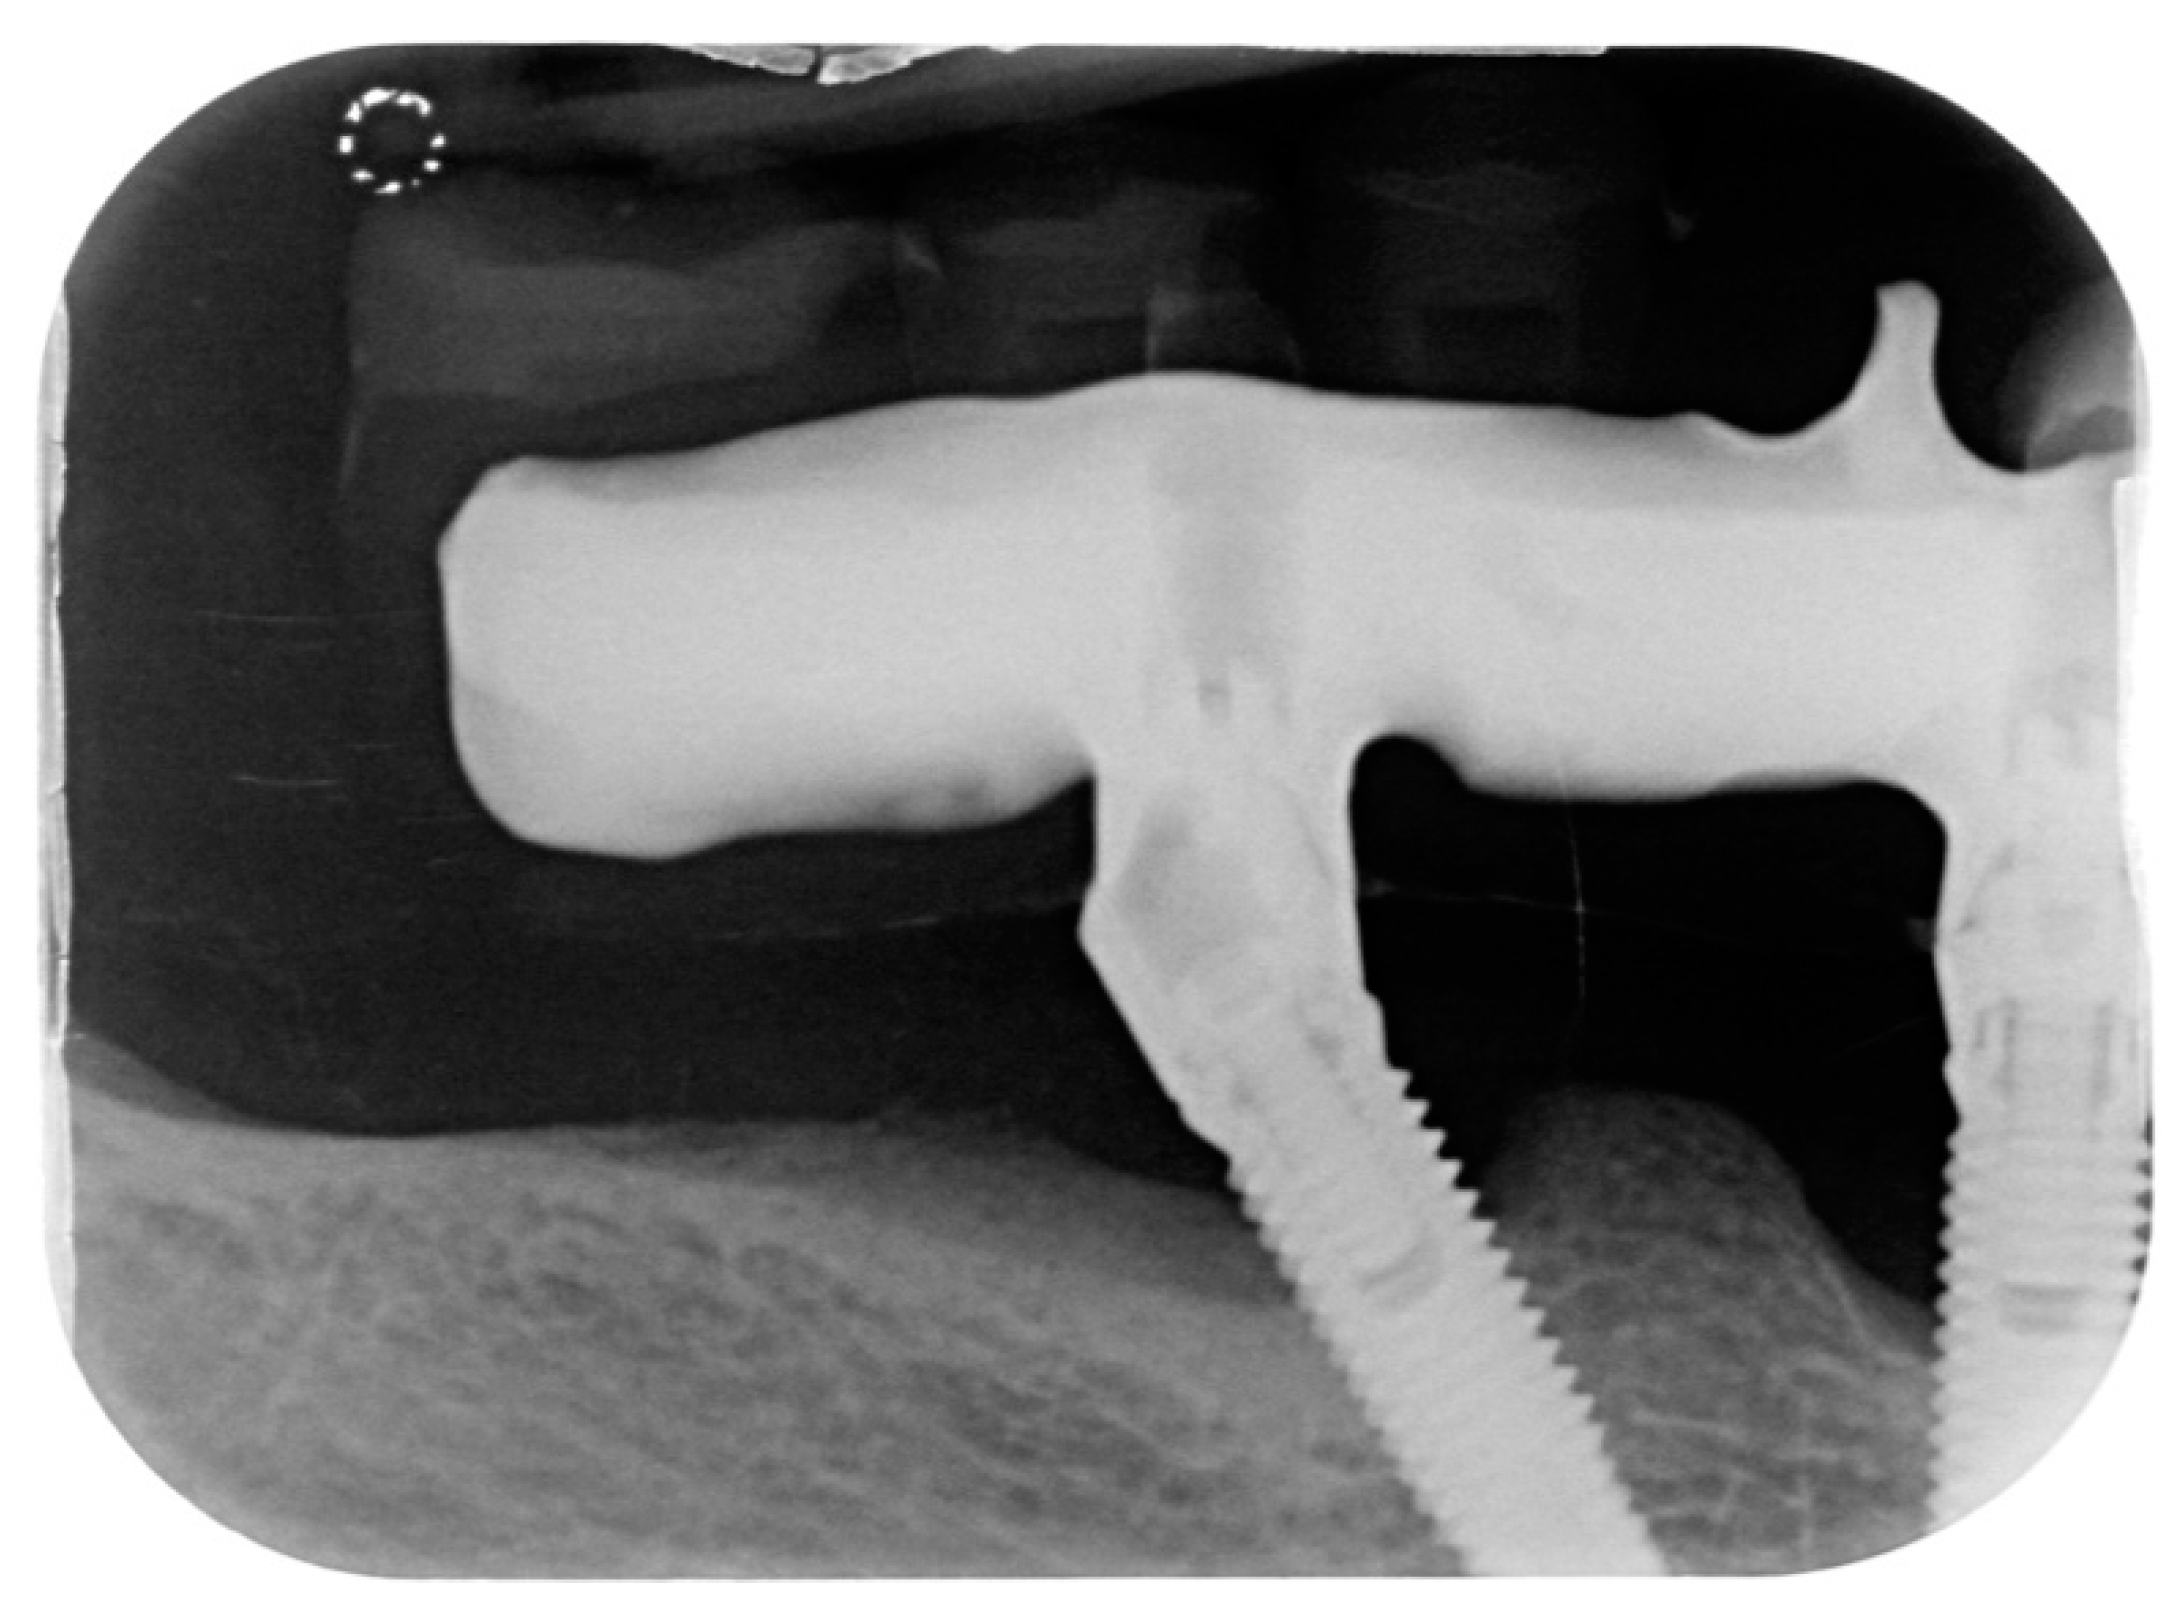

A total of 23 cases of peri-implantitis (patient-level) were registered, representing an overall prevalence of 11.3%. Only one diabetic patient (type 2) developed peri-implantitis (5.3%) whereas one subject with type 1 diabetes experienced multiple implant failures due to a failure of osseointegration. Figure 1 and Figure 2 show radiographic evidence of peri-implantitis in one diabetic (Figure 1) and one non-diabetic patient (Figure 2). Figure 1 and Figure 2 show radiographic evidence of peri-implantitis in one non-diabetic (Figure 1) and one diabetic patient (Figure 2). A clinical image of the same diabetic patient is represented in Figure 3.

Figure 2.

Periapical radiograph belonging to the only diabetic patient who developed peri-implantitis.